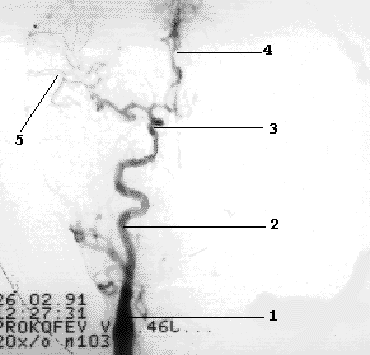

Внутренняя сонная артерия до входа в полость черепа ветвей не дает. Непосредственно после выхода из кавернозного синуса она отдает первую ветвь глазничную артерию, а затем делится на две конечные ветви - переднюю мозговую артерию и среднюю мозговую артерию (Рис 1.5).

Рис 1.5 Интракраниальные ветви ВСА.

1- ОСА, 2- ВСА, 3- сифон ВСА, 4- ПМА, 5- СМА.